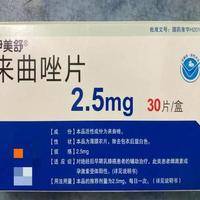

试管进周后吃来曲唑是进入到哪个治疗阶段了?

问题描述:我有朋友因为身体原因无法自然怀孕,然后就去做了详细的生育检查,医生推荐去做试管治疗。后面因为工作忙我也没怎么问过她,昨天约了见面后才知道已经在治疗了,我只记得在吃来曲唑了。想问问吃这个药一般是进入到哪个治疗阶段了呢?最佳回答:无法确定是到哪个治疗阶段了,毕竟来曲唑在试管治疗期间回应用到多个治疗阶段。来曲唑可以促进卵泡发育,因此在试管临床上在促排阶段的应用比较多。不过对于有乳腺疾病或者需要...